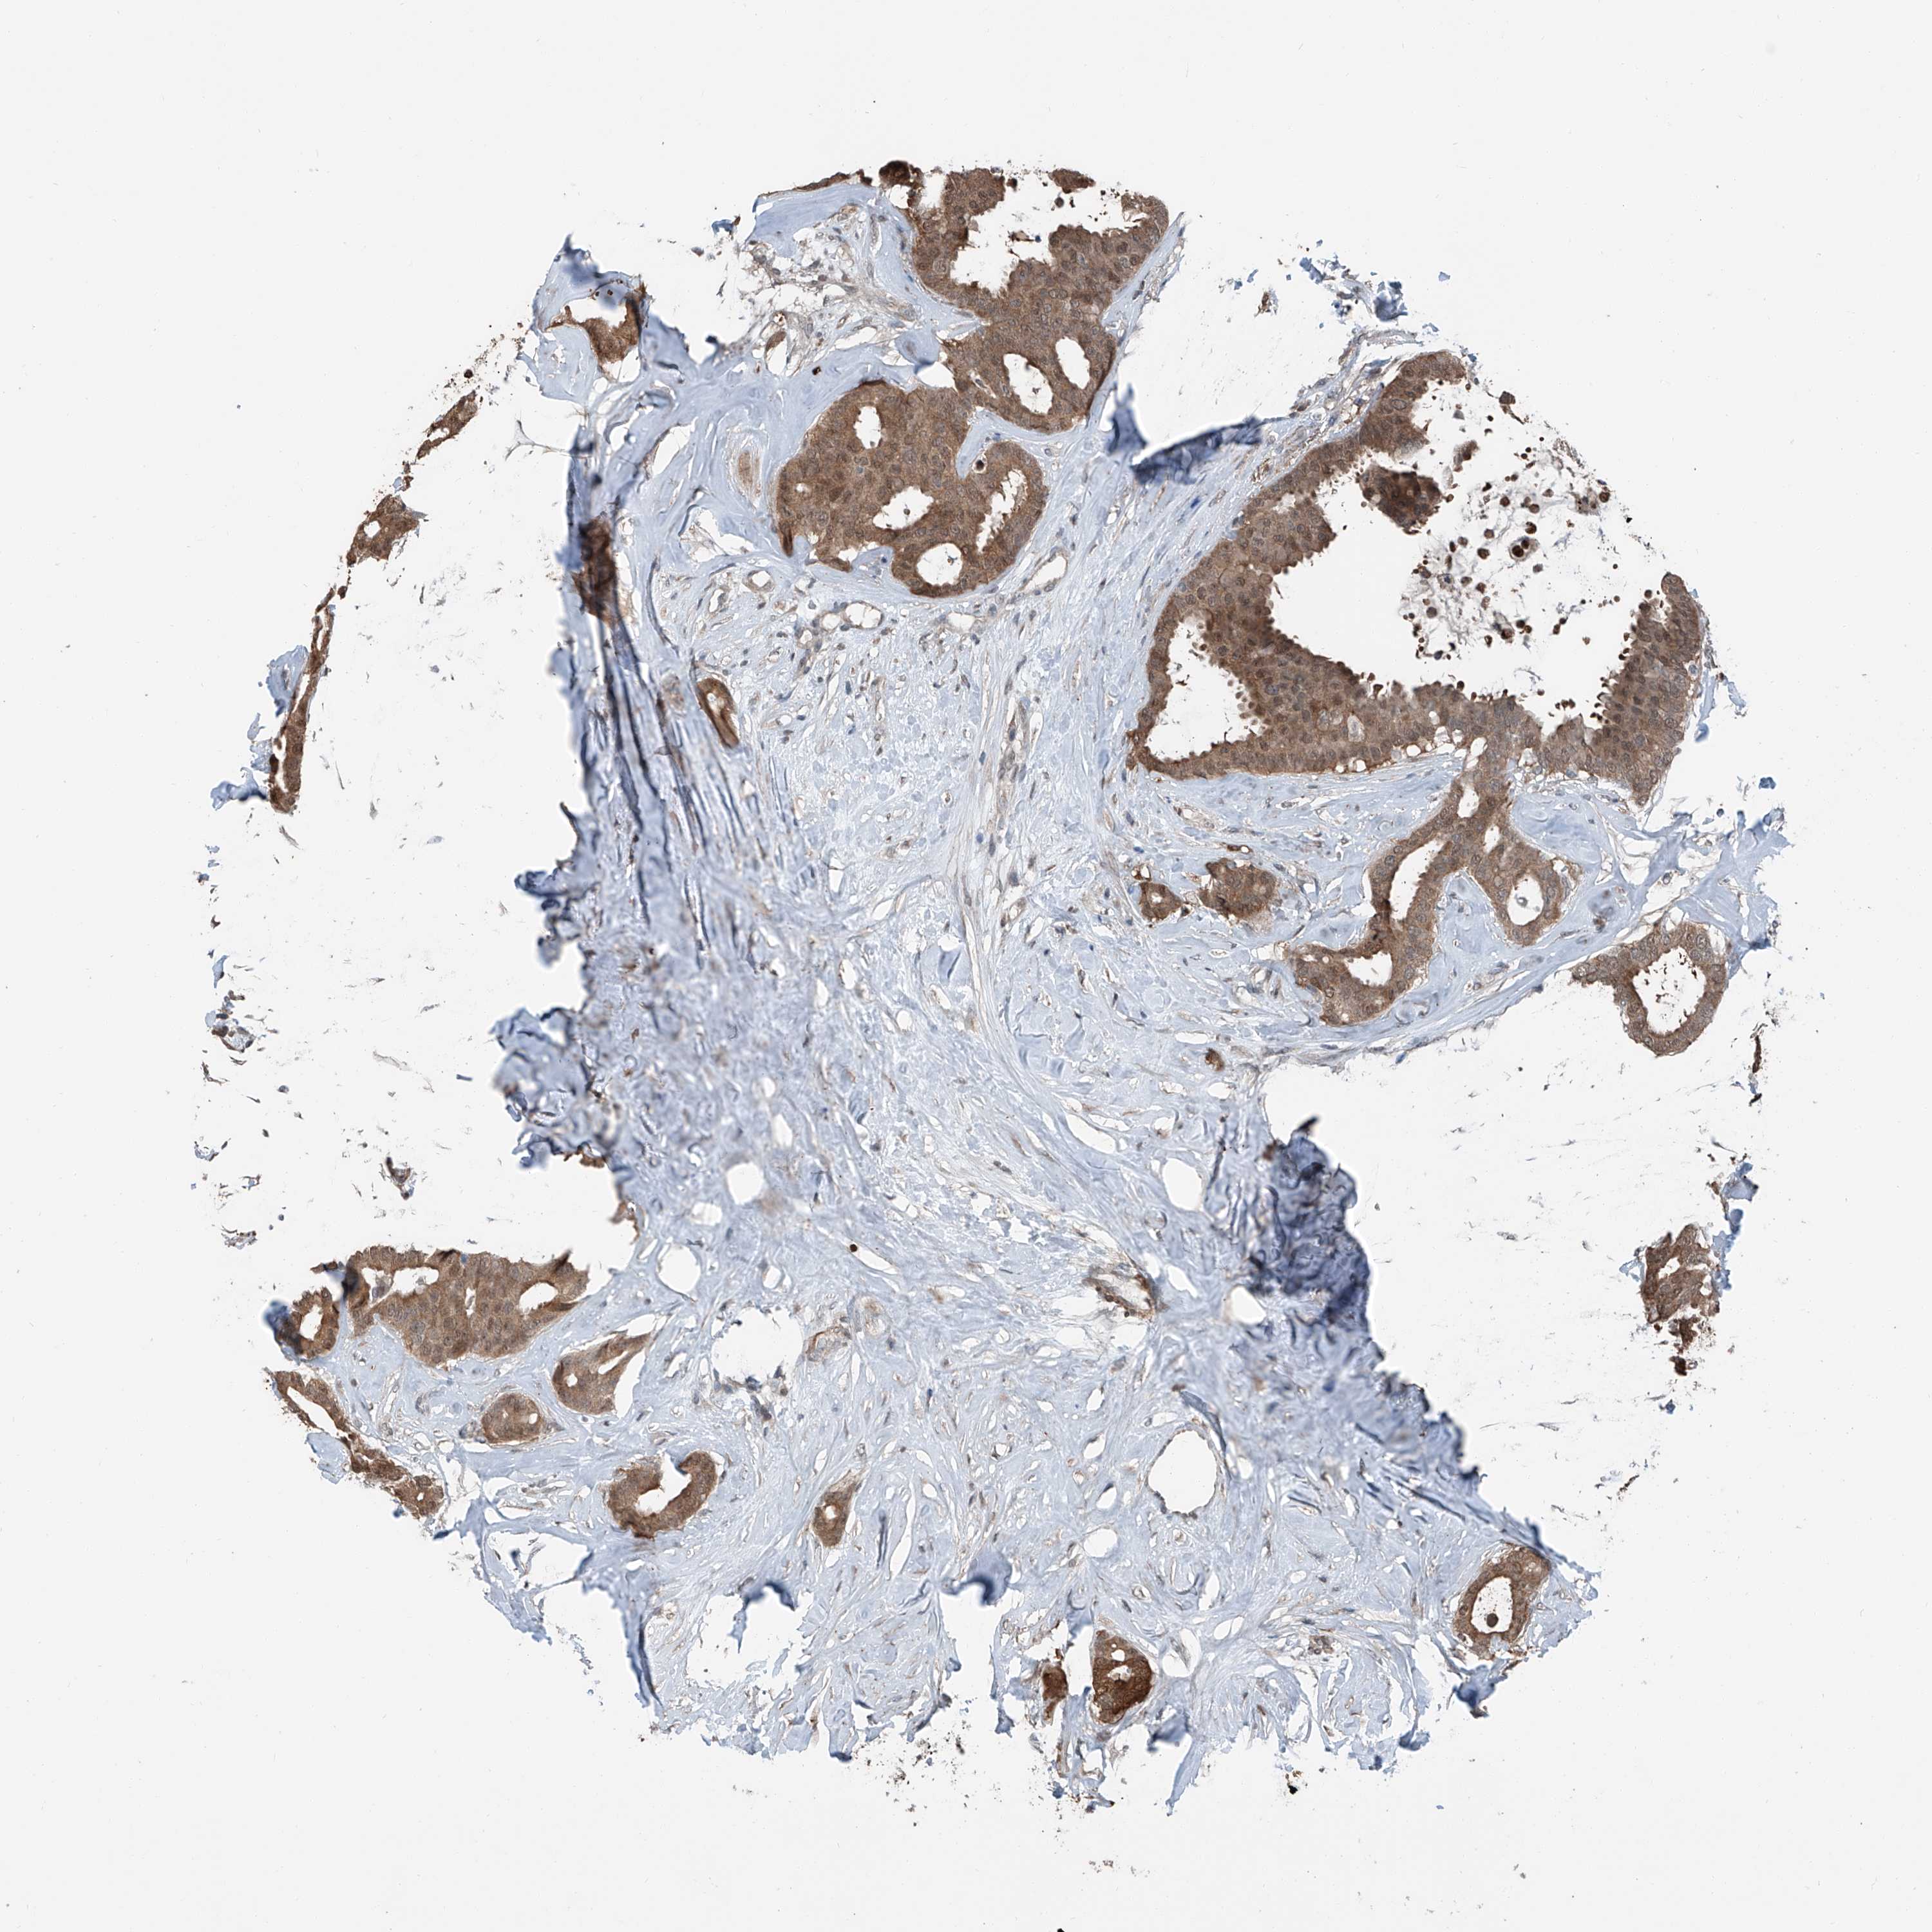

CANCER BREAST CANCER Show tissue menu

BRCA TCGA BRCA VALIDATION PROTEIN EXPRESSION